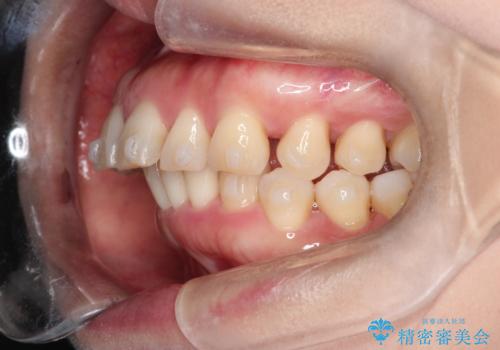

【インビザライン】出っ歯を治したい

- 前歯が出ていることを主訴に来院されました。

インビザラインにて臼歯部の遠心移動及びIPRを行なっています。

叢生量が多いケースでしたが、綺麗な歯並びとなり患者様にも満足していただきました。

非抜歯矯正のため口元の変化はありません。